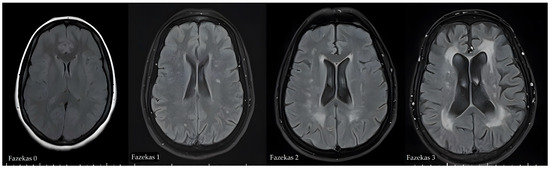

Relationship Between Carotid Artery Anatomy and Geometry and White Matter Hyperintensities and Accompanying Comorbid Factors

Background/Objectives: This study aimed to investigate the relationship between carotid artery anatomy and geometry and white matter hyperintensities (WMH) and to determine whether it is a risk factor for the disease. Methods: The geometry and anatomy of both carotid arteries were evaluated with the three-dimensional vessel model obtained from the computed tomography angiography (CTA) data, and the segmentation software calculated the geometrical features of the arteries. In this model, vascular diameter, vascular cross-sectional area, carotid bifurcation and internal carotid artery (ICA) angles, as well as ICA tortuosity index (TI) measurements of the common carotid artery (CCA) and ICA were determined. Results: Compared with the non-WMH group, increased carotid bifurcation and ICA angle and higher ICA TI values were found in the WMH group (p < 0.001). In multivariate regression analysis, increased carotid bifurcation angle, higher ICA TI values, age, hypertension, and stroke history were identified as independent risk factors for the development of WMH (p < 0.05). In addition, age, carotid bifurcation angles and ICA angles were found to be associated with the severity of WMH (p < 0.05). Conclusions: Considering the vascular pathologies involved in the pathogenesis of WMH, identifying these risk factors may help determine individuals who are at an increased risk. Full article

Figure 1